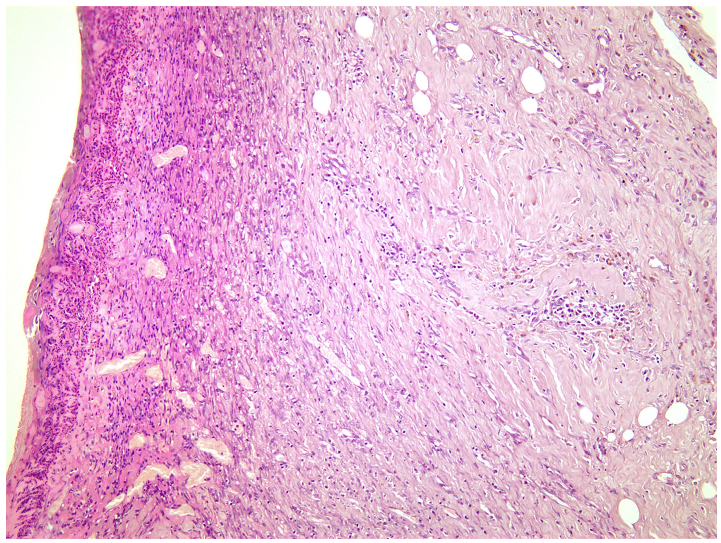

—fibrin clot,

—granulation tissue,

—adipose tissue.